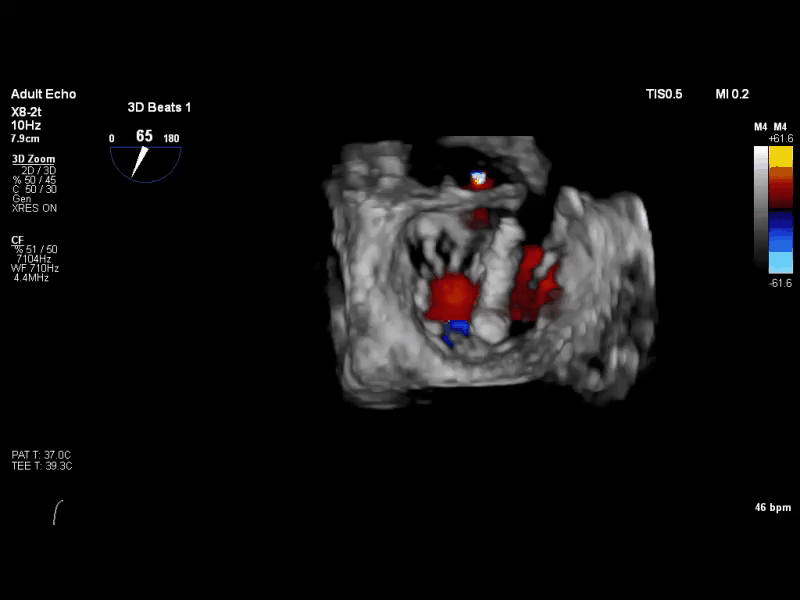

术前TEE 3D COLOR

经食道超声心动图(TEE)提示:二尖瓣病变Carpentier II型,DMR,二尖瓣2区反流及P2腱索断裂并瓣叶脱垂,Gap 6 mm,Width 15 mm, 瓣口面积6.7 cm²,2区前叶长20 mm,后叶长19 mm。MR4+,反流束来自于2区,偏心性反流束,指向前叶;VC 11 mm。房间隔穿刺空间约4.5 cm。